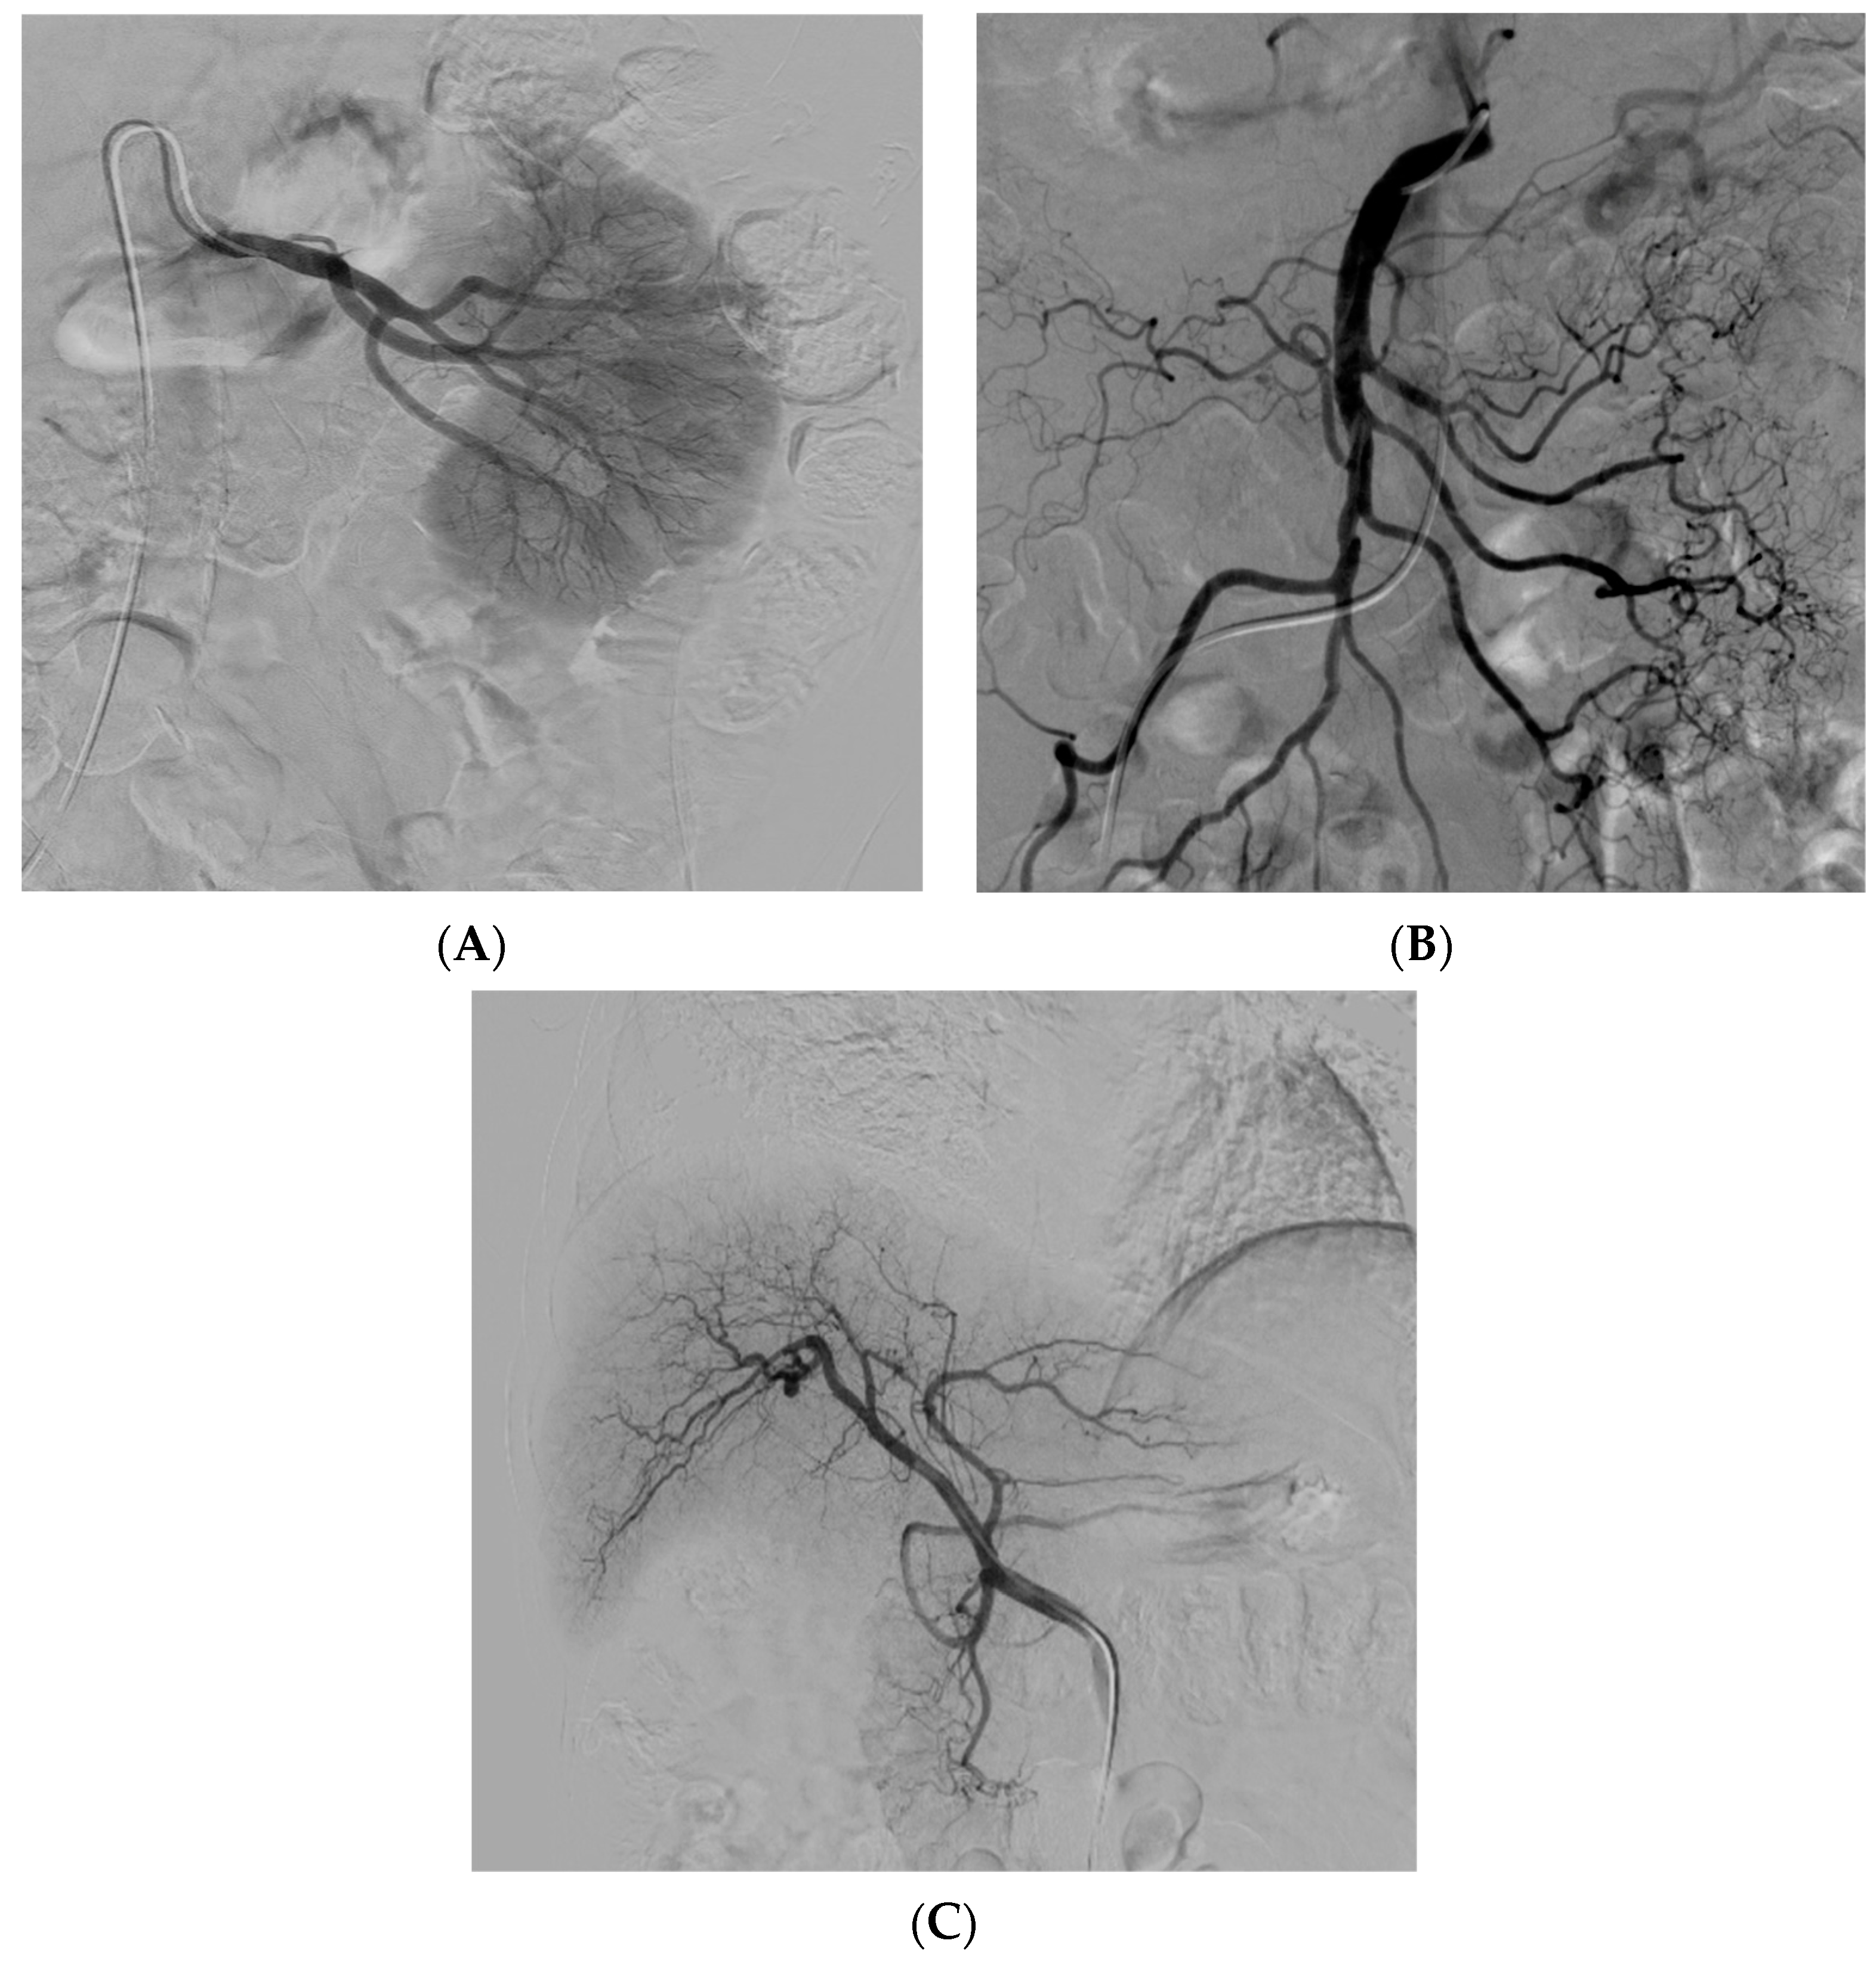

3.5. Peripheral Arterial Disease

- Mao, Q.; Wang, W.; Xu, T.; Zhang, S.; Xiao, L.; Chen, D.; Jin, H.; Tong, P. Combination treatment of biomechanical support and targeted intra-arterial infusion of peripheral blood stem cells mobilized by granulocyte-colony stimulating factor for the osteonecrosis of the femoral head: A randomized controlled clinical trial. J. Bone Miner. Res. 2015, 30, 647–656. [Google Scholar] [CrossRef] [PubMed]

- Pan, J.; Ding, Q.; Lv, S.; Xia, B.; Jin, H.; Chen, D.; Xiao, L.; Tong, P. Prognosis after autologous peripheral blood stem cell transplantation for osteonecrosis of the femoral head in the pre-collapse stage: A retrospective cohort study. Stem Cell Res. Ther. 2020, 11, 83. [Google Scholar] [CrossRef] [PubMed]